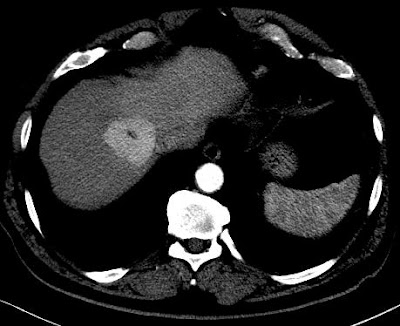

CT will show FNH as a vascular tumor, that will be hyperdens in the arterial phase, except for the central scar.

Above a typical FNH with a central scar that is hypodens in the portal venous phase .